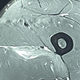

Predaja Novaka Đokovića v polfinalu Odprtega prvenstva še dviga prah. Tenisač je na družbenem omrežju X zdaj objavil sliko magnetne resonance natrgane stegenske mišice za vse "strokovnjake" za športne poškodbe. …